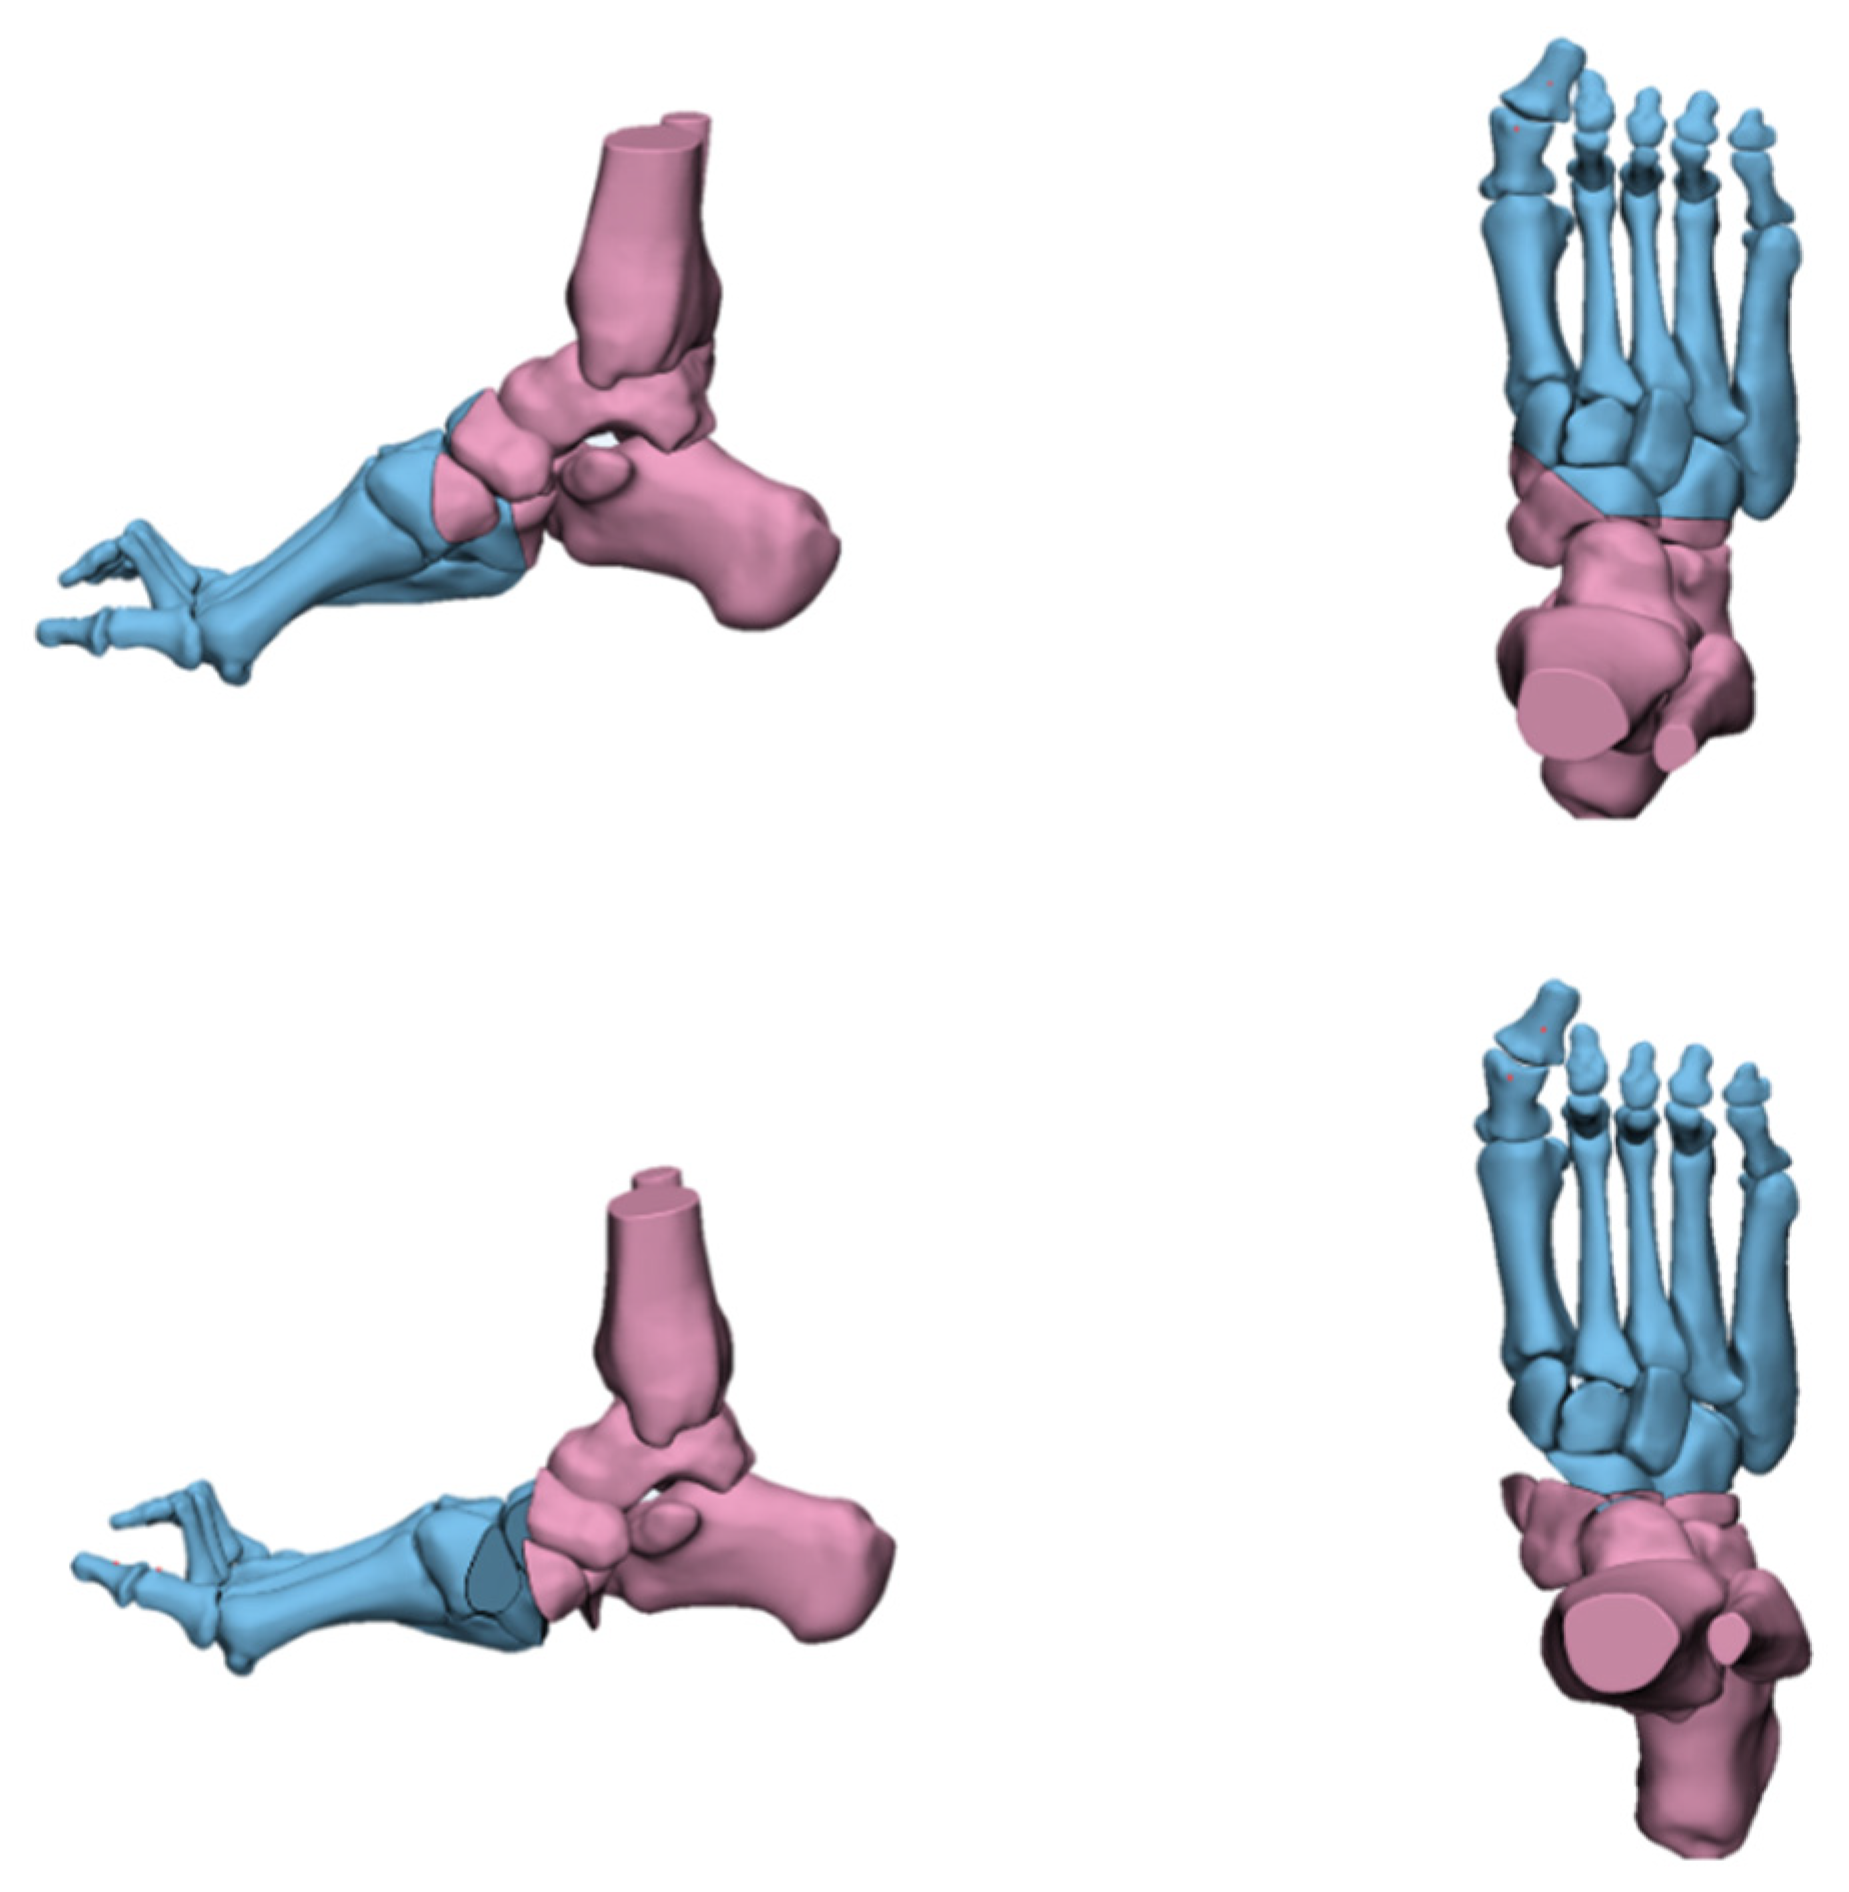

4.2. Radiological Evaluation